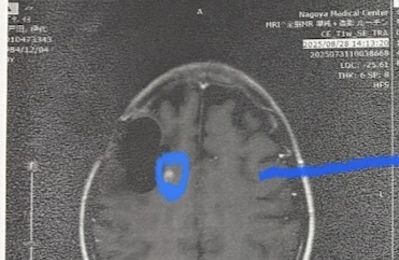

前回のブログ内容同様、今月2日に再発の診断を受け、その4日後に更に主治医の方が他の先生との話し合いの後に手術内容を決めたことを伝えるとのことで、先生からの連絡で(そんな事は初めてで驚きました。)急遽6日に手術のおおまかな内容を聞きに行きました。添付写真(左右反転なので左に写っているのは右脳です)の1枚目が今回見つかった新たな腫瘍(再発したもの)です。それを可能なだけ取り切るとのことです。更に幸運な…